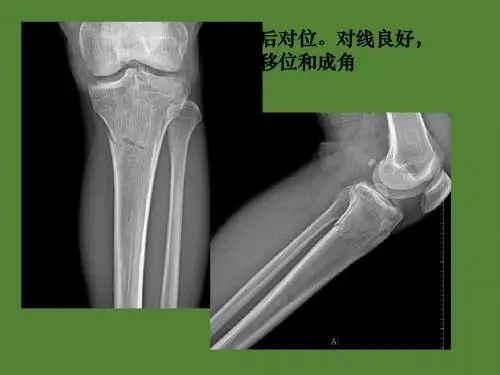

第一节 四肢骨关节X线解剖及变异

一、成人正常管状骨X线解剖 (一)骨干(diaphysis) 1、骨膜。2、骨皮质(营养动脉孔)。3、骨松质(骨小梁、骨 髓间隙)。4、骨髓腔。5、正常解剖变异(致密骨岛、软骨岛、 发育障碍线、骨骺线遗迹)。 (二)骨端(bony end) 二、关节的X线解剖 (一)关节间隙(joint space):关节骨端之间的空隙。它包括 解剖的关节软骨,关节内纤维软骨,关节腔及关节液。 (二)关节面(joint surface):骨端边缘光滑锐利的骨密质。 (三)关节囊及周围软组织(articular capsule and peripheral soft tissue):在脂肪和疏松结缔组织衬托下可见韧带及关节囊。